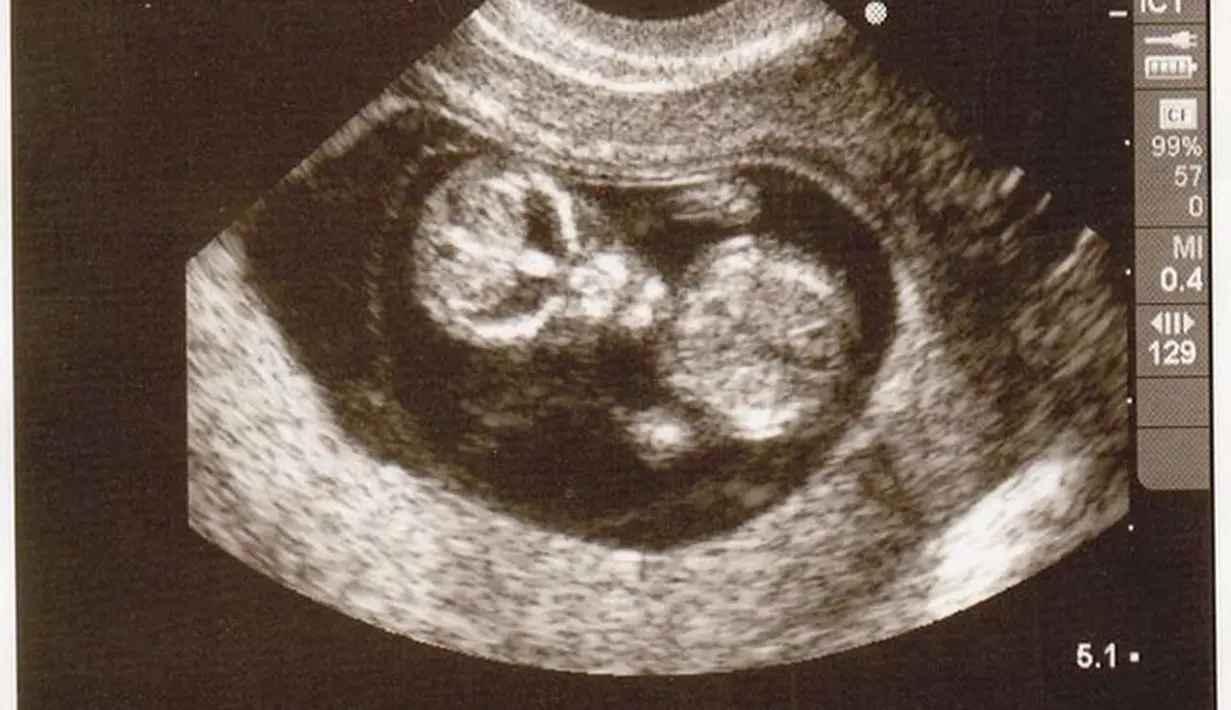

Ketika seorang ibu tengah mengandung, tidak jarang ia akan melakukan foto scan atau USG terhadap kandungannya. USG ini sendiri biasanya dilakukan untuk mengetahui jenis kelamin buah hati di dalam kandungan juga mengetahui tumbuh kembangnya.

Dan ketika melakukan USG kandungan, setiap ibu juga ayah janin berharap bahwa hasil USG begitu menggemaskan dan janin terlihat jelas. Sayangnya, tidak jarang hasil USG justru terlihat sangat menyeramkan, bikin merinding atau bahkan seperti ada sosok hantu di dalamnya. Seperti halnya hasil USG berikut ini.

Hasil USG ini memperlihatkan sesuatu yang menyeramkan dan bikin merinding karena seolah ada sosok hantu telah tertangkap kamera USG. Penasaran dengan foto-fotonya? Simak baik-baik galeri fotonya di bawah ini. Jika kamu tak berani melihatnya sendiri, usahakan untuk mengajak teman untuk melihatnya.